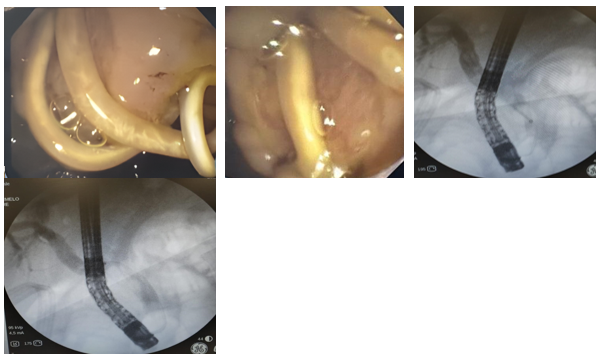

In addition, mild ectasia of the extrahepatic bile duct was documented with a linear image inside it, suggestive of a hepatobiliary endoprosthesis. However, the patient had no history of placement of said endoprosthesis, so the treating service considered the possibility of ascaris and decided to perform a new ERCP. During this procedure, a non-dilated intrahepatic bile duct and a dilated extrahepatic bile duct, measuring 10 mm, with a filling defect throughout the common bile duct, were observed (Annex 2). The bile duct was explored with an occlusion balloon and Dormia basket, extracting 5 ascaris one by one through the mouth.

Endoscopic management as a safe and effective alternative for the treatment of biliary ascariasis, especially in cases complicated by cholangitis or obstructive jaundice. Endoscopic extraction allows rapid resolution of symptoms and prevents serious complications.8 The possibility of spontaneous elimination of juvenile stages of Ascaris lumbricoides orally, a rare but documented phenomenon. This finding highlights the importance of considering specific epidemiological and clinical factors in each region.9